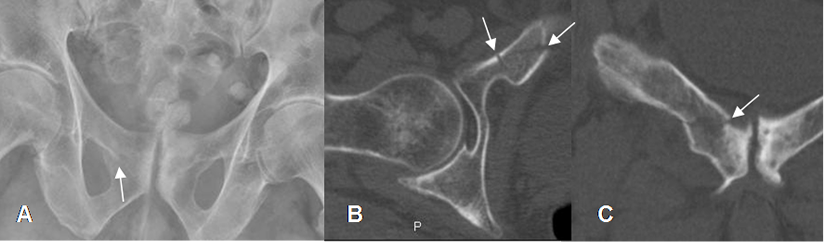

Fig 68. Fractura del pubis.

A: Rx AP. Cambios degenerativos en la sínfisis púbica e irregularidad en la parte medial del agujero obturador, lo que hace sospechar fractura.

B: TAC axial y C: TAC reconstrucción coronal. Se confirma fractura oblicua, en el pubis derecho.